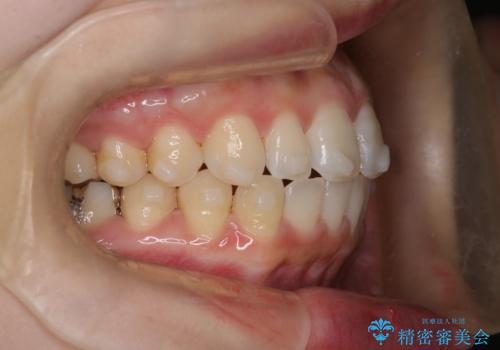

【インビザライン】前歯が出てるのを治したい

- 前歯の凸凹と前突を主訴に来院されました。

インビザラインにて治療をおこない、歯並びを改善することができました。